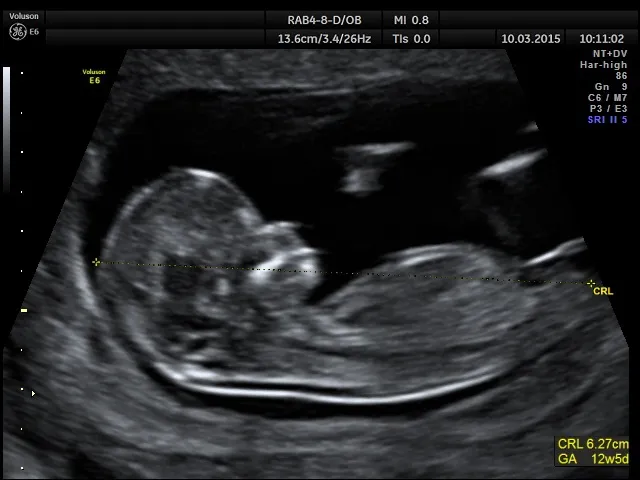

Na czym polega pomiar CRL (długość ciemieniowo-siedzeniowa)?

Kluczowym parametrem wykorzystywanym podczas USG w pierwszym trymestrze do określenia wieku ciąży jest pomiar CRL (Crown-Rump Length), czyli długość ciemieniowo-siedzeniowa płodu. Jest to odległość mierzona od czubka głowy (ciemienia) do najniższego punktu pośladków (siedzenia) dziecka. Ten konkretny pomiar jest niezwykle ważny, ponieważ w pierwszych tygodniach ciąży płód nie jest jeszcze w pełni wyprostowany, a pomiar CRL pozwala na najbardziej precyzyjne oszacowanie jego wielkości i, co za tym idzie, wieku.

Dlaczego właśnie USG między 11. a 14. tygodniem jest najdokładniejsze?

Optymalne okno czasowe dla wykonania USG w celu ustalenia terminu porodu to okres między 11. a 14. tygodniem ciąży. To właśnie wtedy pomiar CRL jest najbardziej miarodajny. Wcześniej płód jest zbyt mały, aby pomiar był precyzyjny, a później, po 14. tygodniu, zaczynają pojawiać się indywidualne różnice w tempie wzrostu między dziećmi. W tym idealnym przedziale czasowym różnice w rozwoju płodów są minimalne, co pozwala na oszacowanie terminu porodu z dokładnością do +/- 5-7 dni. To znacznie większa precyzja niż w przypadku datowania na podstawie ostatniej miesiączki.